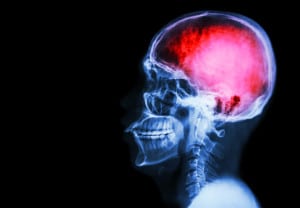

Explicación: ¿Qué pasa con el cerebro?

• Adentro del cráneo el tejido es muy suave, pero la base del cerebro es muy rígida tiene aspectos rasposos

• Cuando la cabeza se mueve violenta y rápidamente las células se inflaman y el cerebro incrementa su presión interna.

• El cerebro tiene 3 componentes: tejido cerebral (células), agua (liquido cefalorraquídeo) y sangre. Cuando se presenta un golpe, y se incrementa la presión intracraneal, el agua no se comprime fácilmente por lo que se altera es el tejido cerebral.